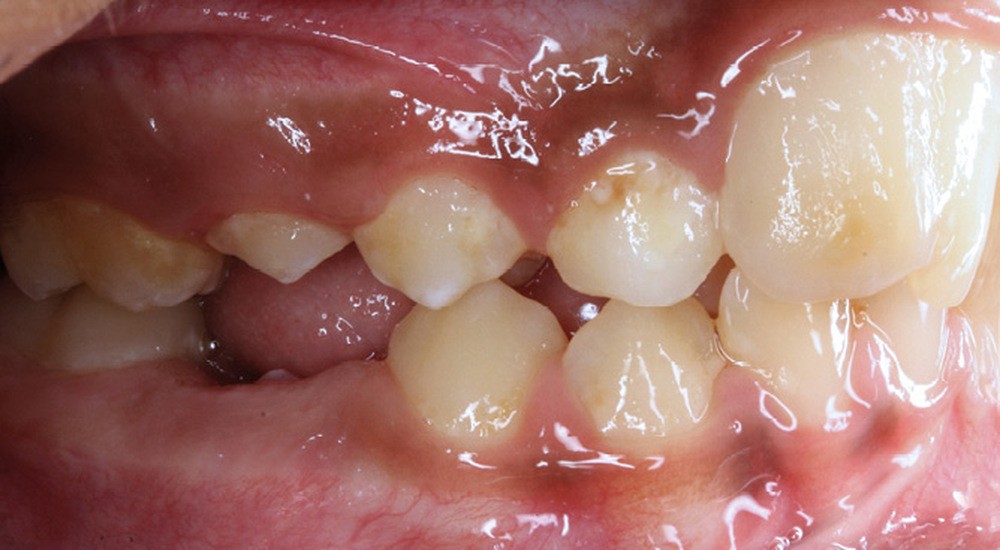

Le profil est convexe et associé à une inocclusion labiale au repos. Il s’agit d’une classe II squelettique sur un schéma facial normodivergent. Les rapports occlusaux sont de classe II bilatérale (complète au niveau molaire) avec des incisives inférieures vestibulo-versées. La 21 est géminée et la 11 vraisemblablement fusionnée avec un germe surnuméraire, sans altération de la formule dentaire. Du fait du diamètre mésiodistal fortement augmenté des incisives centrales, et du manque de place à l’arcade maxillaire qui en découle, les 12 et 22 sont en inversé d’occlusion en palato position. Les 53 et 63 sont persistantes sur l’arcade avec une inclusion en transposition incomplète de la 13, dont la cuspide se situe entre la racine de la 12 et celle de la 11 résorbée (fig. 1d-g).